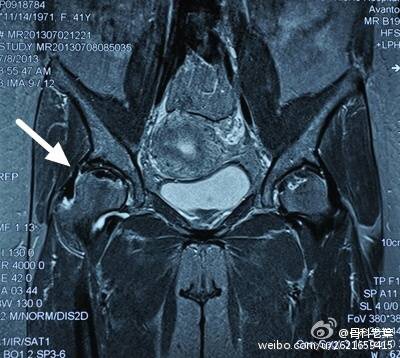

II期 病人有髋部症状,磁共振出现异常,X线片显示股骨头出现透光和硬化改变

III期 磁共振出现异常,X线片显示软骨下塌陷(新月征),股骨头内出现空洞,股骨头没有变扁

II期和III期的患者治疗方法相同,因为此时股骨头虽然还没有变形,暂时还不需要行人工关节置换术,但是股骨头已经出现空洞,随时股骨头就会塌陷变形,所以单纯的股骨头减压术是不能达到治疗效果的。这时就需要在股骨头减压的同时,植入一根支撑棒,顶住股骨头空洞区,防止股骨头在负重的情况下过早塌陷。其他治疗同之前相同,口服以上药物,定期复查,密切观察病情发展,尽量避免重体力劳动和爬山爬楼。

另附典型病例若干: